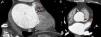

Case 3A 58-year-old man with known coronary disease, who had previously undergone angioplasty of the proximal anterior descending artery, experienced recurrence of angina and was accordingly referred for cardiac CT to assess stent patency. The exam excluded progression of coronary disease but revealed asymmetrical left ventricular hypertrophy and a ventricular septum of 36mm (Figure 3), compatible with hypertrophic cardiomyopathy. A cardioverter-defibrillator was implanted and to date no appropriate therapies have been recorded.